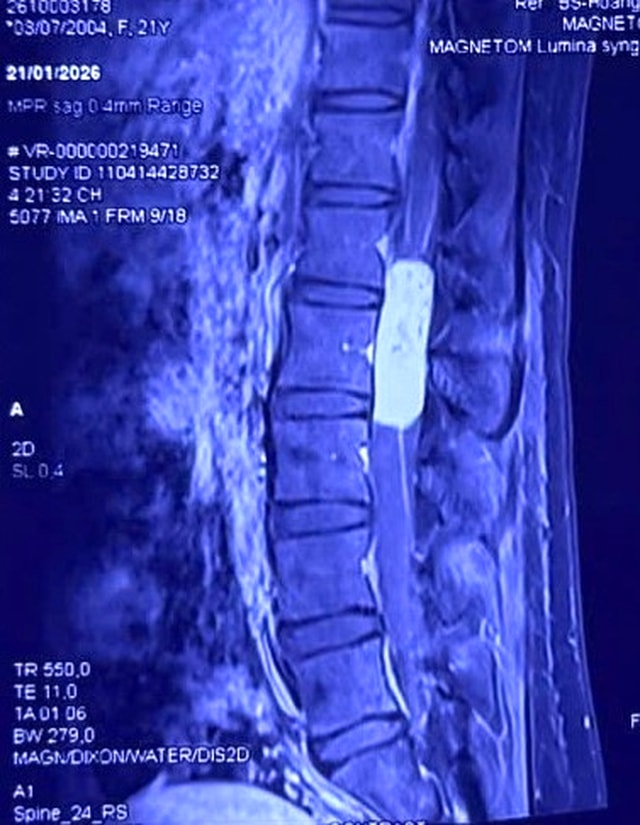

Kết quả chụp cộng hưởng từ (MRI) cho thấy chị H.L. có một khối u màng não tủy dài gần 10cm, kéo dài từ đốt sống L1 đến L3. Khối u "ôm trọn" tủy sống và các rễ thần kinh đuôi ngựa – vùng kiểm soát vận động, cảm giác của toàn bộ hai chi dưới.

Đây là ca bệnh đặc biệt nguy hiểm. Bệnh nhân vừa sinh con, thể trạng còn yếu, nguy cơ mất máu và nhiễm trùng cao. Khối u lớn đã làm tủy sống bị đẩy dẹt, mạch máu nuôi tủy bị xâm lấn. Chỉ một sai sót nhỏ trong lúc phẫu thuật cũng có thể khiến bệnh nhân liệt vĩnh viễn.